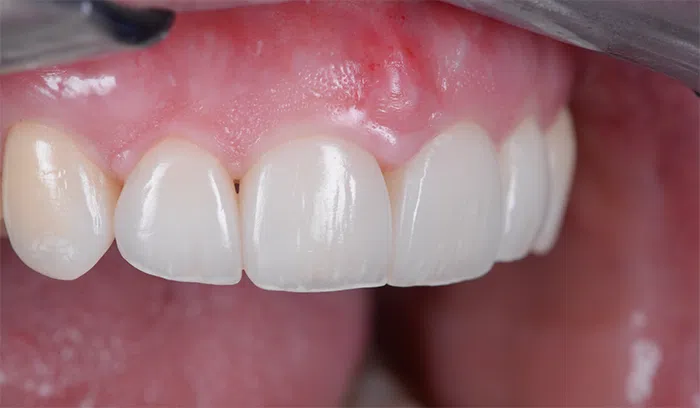

După

Caz de estetică dentară – Fațete ceramică presată E-Max

Provocarea acestui caz a fost în prepararea minim invazivă a dinților centrali rotați și a obține o formă și o culoare cât mai naturală, pacienta dorind un caz de estetică dentară ce să nu fie observabil.

Pacienta a beneficiat de corecție gingivala cu laser pentru uniformizarea asimetriilor gingivale, tratamente endodontice de canal sub microscop, obturațiile vechi (plombe) schimbate cu materiale de compozit cu particule nanoceramice, și fațete dentare din ceramică presată E-Max.

Termen de finalizare 2 săptămâni de la amprentarea finală.